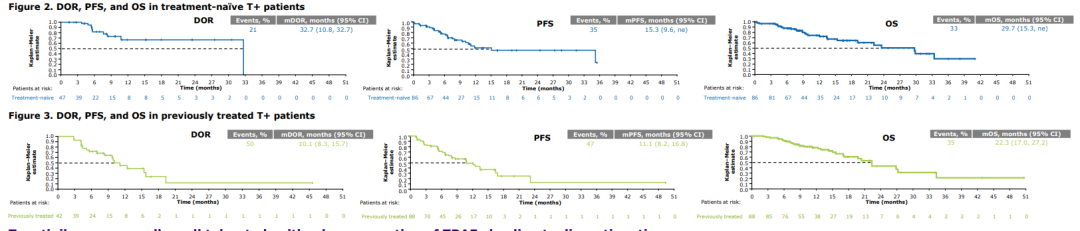

近年来,何志勇主任团队在双倍剂量伏美替尼治疗三代EGFR-TKI耐药的临床实践中,做了临床层面的探索,并总结了临床经验。近2年来,团队共应用双倍剂量伏美替尼18例,其中,3例是初治脑转移患者,15例是三代EGFR-TKI耐药且经历多线治疗后的患者,治疗都能达到不同程度的肿瘤缩小,总体缓解率为86%(13/15),中位疾病缓解时间为4个月,最长的超过17个月。

另据介绍,三代EGFR-TKI耐药后肺癌患者的治疗,是目前临床上的难点和热点。近年来,何志勇主任团队致力于在临床中探索不同的行之有效的策略。除了双倍剂量伏美替尼,团队还采用节拍治疗克服三代EGFR-TKI耐药,总结了28例患者的临床数据,疾病控制率达到89.3%